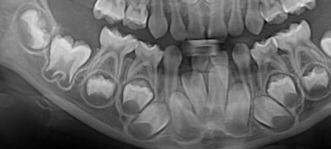

5살 정도의 유치열의 파노라마이다. 유치 아래로 영구치 치아싹이 보인다. 치배라고 한다. 사실 이런 이미지에 익숙한 사람들은 치과 종사자가 유일할것이다. 하지만 잘 보면 유치 아래로 한번 더 영구치가 나는 일생일대의 기회가 자라고 있다.

그래서 그 사실을 사랑과 새싹에 비유한 글을 써보았다. 실제 x-ray 파노라마상에서도 치배는 방울속에 둘러쌓인 하트 같아 보이기도한다. 나의 치아에 대한 각별한 사랑의 눈때문일수도 있지만..